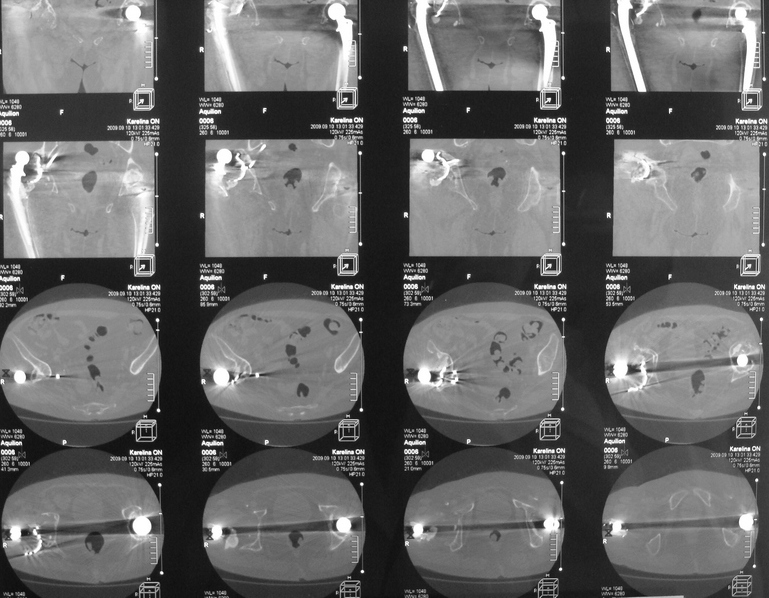

Уважаемые коллеги,в клинику поступила пациентка 51год с нестабильным антипротрузионным кольцом и вывихом эндопротеза. В течени длительного времени у пациентки ревматойдный полиартрит с приемом преднизолона. В 1994 году произведено эндопротезирование правого тазобедренного сустава бесцементным эндопротезом Biotronic. В 2000году по поводу нестабильности эндопротеза проведено ревизионное вмешательство-удаление чашки и ножки, некрэктомия. Установка антипротрузионного кольца, цементной чашки и ревизионной цементной ножки Beznoska. В 2007году выявлена клиникорентгенологическая картина нестабильности кольца. В 2008году пациентка упала, произошел вывих эндопротеза и дислокация кольца с переломом винтов. Планируем ревизионное вмешательство-удаление кольца, чашки, винтов, пластика верхнего края вертлужной впадины массивным аллотрансплантатом с последующей установкой антипротрузионного кольца типа Burch-Shneider. Прошу коллег занимающихся ревизионным эндопротезированием высказать свое мнение.PS:у больной в 1998 году установлен цементный эндопротез Beznoska левого тазобедренного сустава и в 2003 году установлен цементный эндопротез De Puy LCS правого коленного сустава.

Ситуация непростая, во время операции может оказаться дефект не только передне-верхнего отдела ВВ, но и слабость задней стенки. В этом случае результаты установки кольца Б-Ш могут быть не столь оптимистичны. Использование массивного аллографта опасно развитием позднего остеолиза и как следствие - нестабильности конструкции, плюс к этому-реальная опасность инфекционного осложнения. В последнее время (и мы будем говорить об этом на Вреденовских чтениях - маленькая рекламка:)) мне все больше импонирует ТМТ, это трабекулярный металл с очень высокой пористостью. Если рим ВВ позволяет хоть немного зацепиться полусферической чашкой, то успех гарантирован. При наличии сегментарного дефекта лучше в этой ситуации использовать трабекулярные аугменты и женить с ТМТ ревизионной чашкой при помощи цемента. Все небольшие дефекты мы заполяем костной стружкой (алло) в последнее время стали применять остеосет Т (с тобромицином). Если же совсем все плохо, то тогда палочкой-выручалочкой является кольцо Б-Ш., которое можно установить по ситуации, а анатомические углы выставить ПЭ вкладышем.